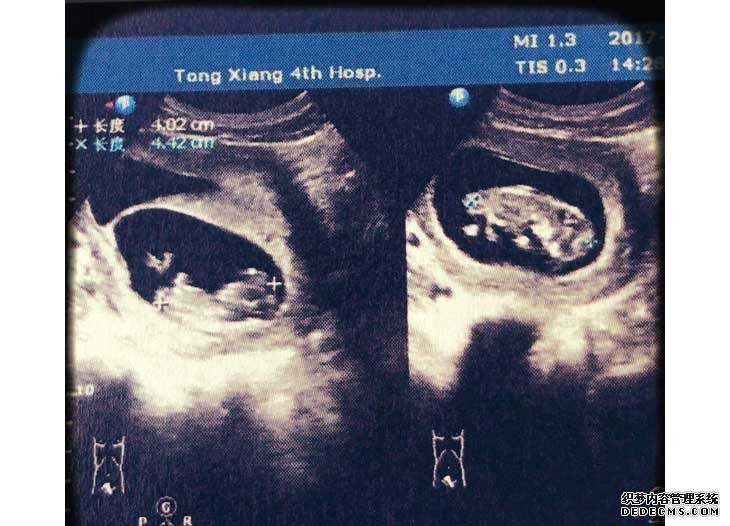

B超檢查懷上雙胞胎V2G育兒資訊網-育兒常識全方位解讀,助您開啟好孕之旅

那幾天也就安心地躺在床上,小心翼翼地。一回國后大概過了14天左右,進行驗血,結果血值翻倍8080,心想有可能雙胎,終于熬到B超的時候,大夫也說雙胞胎,都有了胎心,那一刻還是懵的,回家緩了幾天,失眠了幾天,突然有了前所未有的喜悅。V2G育兒資訊網-育兒常識全方位解讀,助您開啟好孕之旅